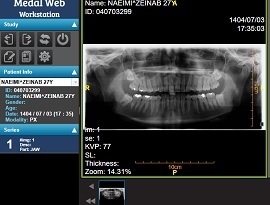

پانورکس یا رادیولوژی دندان نوعی رادیوگرافی از تمام دندان ها و استخوان فک بالا و پایین است که در آن از اشعه ایکس برای تصویربرداری استفاده می شود. از ابتدا تصاویر پانورکس پس از اتمام تصویربرداری بر روی فیلم رادیولوژی به چاپ می رسیده اما امروزه با پیشرفت فناوری از بارکد دوبعدی برای ارائه تصاویر استفاده می گردد.

پانورکس یا OPG رادیوگرافی دوبعدی از کل دندانهاست که غیرتهاجمی و بدون درد بوده و علاوه بر دندانهای بالا و پایین ، فک بالا و فک پایین و استخوانهای اطراف را نیز بخوبی نمایش می دهد. در این نوع تصویربرداری اشعه ایکس برای گرفتن تصاویر بکار گرفته می شود و بر خلاف رادیوگرافی قدیمی بجز دندان همه مناطق فک را نیز مشخص می کند. جالب است بدانید که پانورکس در تشخیص بیماری پریودنتال پیشرفته ، تشخیص سرطان دهان در مراحل اولیه و بررسی اختلال مفصل TMJ یا گیجگاهی فکی موثر است.

تصاویر پانورکس به مانند انواع تصویربرداری پزشکی نظیر رادیولوژی و سی تی اسکن بر روی فیلم رادیولوژی به چاپ می رسیده که با افزایش قیمت فیلم رادیولوژی ( به دلیل وجود فلز نقره در آن و افزایش بهای جهانی نقره و تهیه این فیلم ها از خارج از کشور با قیمت ارز ) به چاپ تصاویر بر روی کاغذ معمولی روی آورده شد. اما کاغذهای معمولی از کیفیت کافی برای مشاهده مشکلات دندانی در پانورکس برخوردار نبود.

در ادامه از سی دی برای رایت تصاویر پانورکس استفاده می شد که با مشکلات دیگری همچون لود نشدن سی دی یا خراب شدن آن و خش افتادن همراه بود. در نهایت امروزه با پیشرفت علوم و فنون ، از نرم افزار فیلم رادیولوژی PPQ برای مشاهده تصاویر پانورکس از طریق بارکد دوبعدی استفاده می شود که به راحتی با موبایل متصل به اینترنت قابل رمزگشایی است.

برای بارکد سازی تصاویر پانورکس از نرم افزار فیلم رادیولوژی PPQ استفاده می شود به گونه ای که در ابتدا تصاویر پانورکس از بیمار گرفته شده و سپس تصاویر به کامپیوتر متصل به دستگاه پانورکس ارسال می گردد. در ادامه کارشناس تصاویر را به فضای ابری نرم افزار فیلم رادیولوژی PPQ ارسال می کند و سیستم ابری نرم افزار یک کد رمزگذاری شده به چاپگر شبکه می فرستد.

کد رمزگذاری شده همان بارکد دوبعدی است که نحوه رمزگشایی آن با دوربین موبایل است بطوریکه با قرار دادن بارکد در راستای دوربین موبایل ، سریعا تصاویر پانورکس بصورت آنلاین در مرورگر موبایل نمایش داده می شود. شایسته است بدانید که لازمه مشاهده تصاویر اتصال به اینترنت می باشد بنابراین از متصل بودن خود به اینترنت اطمینان حاصل کنید. ارائه بارکد دوبعدی تصاویر پانورکس هم به صورت چاپ بر روی کارت مخصوص یا کاغذ و هم بصورت ارسال لینک پیامکی برای شماره همراه بیمار می باشد.